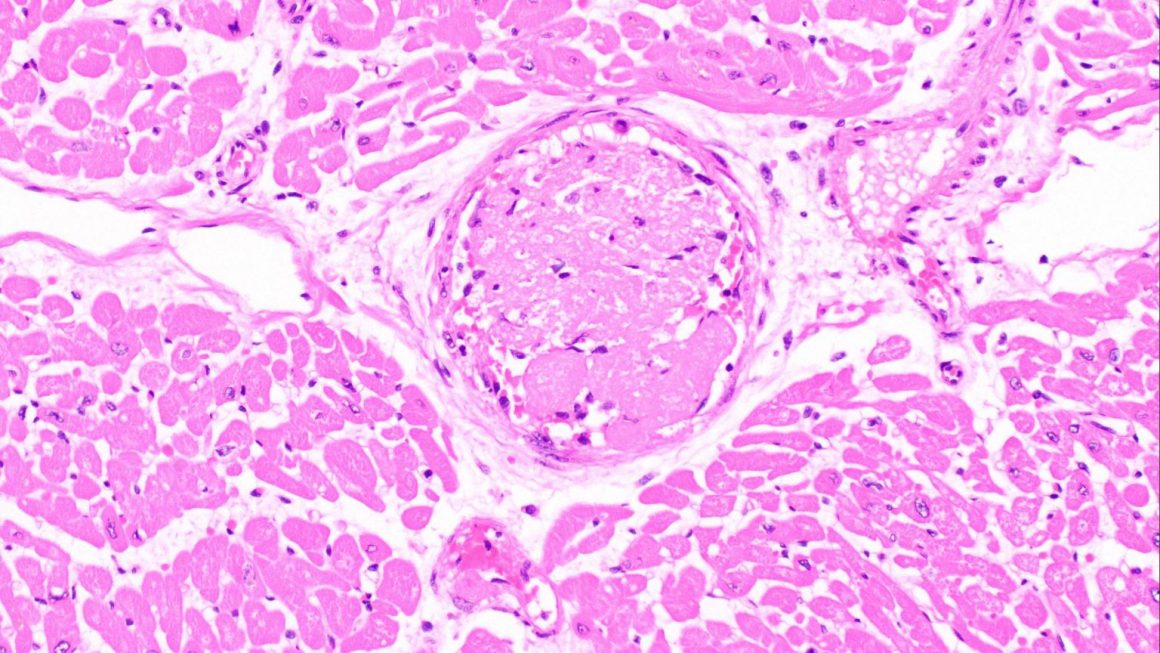

Un estudio pequeño pero detallado llevó a cabo evaluaciones post mortem en el tejido cardíaco de 15 pacientes con COVID-19, incluidos los primeros hallazgos cardíacos post mortem de tres pacientes que habían superado la infección.

En los pacientes con COVID-19, el 33 por ciento de los casos (activos y superados) mostró miocarditis en, al menos, alguna medida; pero el estudio no descubrió evidencia contundente del SARS-CoV-2, o virus que causa el COVID-19, en el tejido cardíaco de los pacientes estudiados.

“El estudio mostró que, a diferencia de otros virus, el COVID-19 parece ejercer un impacto sobre los vasos sanguíneos pequeños del corazón”, señala la Dra. Melanie Bois, patóloga cardiovascular de Mayo Clinic y primera autora del estudio.

Las pruebas con tinción química revelaron coágulos en los vasos sanguíneos pequeños del tejido cardíaco. Estos coágulos sanguíneos fibrosos pueden aún estar presentes incluso después de eliminado el virus, por lo que es factible que se proponga una terapia anticoagulante como tratamiento de los pacientes con COVID-19, posiblemente después de eliminado el virus.

El estudio también cita otras afecciones cardíacas subyacentes que son conocidas por su relación con peores resultados en pacientes con COVID-19. Cabe mencionar que en más del 26 por ciento de los pacientes con COVID-19 estudiados se descubrió amiloidosis cardíaca, que consiste en una acumulación cohesiva de proteínas anormales que interfiere con la capacidad de funcionamiento del corazón.